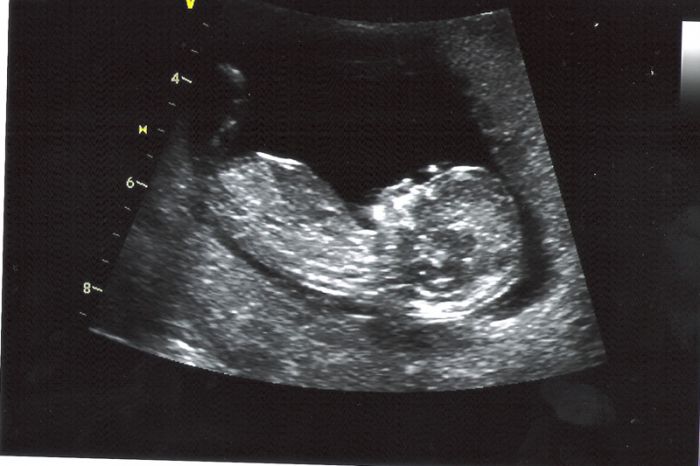

Ahoj holky, všem moc moc děkuji za držení palců:0) Screening dopadl nad očekávání dobře :) jen jsem teď hrozně unavená a trochu bříško bolí, protože se druhej prcek nechtěl moc ukázat :) A v jednu chvíli jsem to zabojkotovala já, protože jak paní doktorka zaryla ultrazvukem do bříška - tak bylo vidět, jak malej do něj buší ručičkou :0)) což sem neustála a vyprskla smíchy :0)))Od pondělka pěkně povyrostli - jeden 55mm a druhý 58mm - tp 25.2. Pohlaví nevíme, ale zatím vše vyšlo tak, že nemusíme ani na plodovku, což vůbec nikdo nečekal, že by mohlo vyjít takhle dobře v mém věku :0) Jsem šťastná jak blecha :) Tak teď ještě počkat až se holky vrátí taky se skvělými výsledky :0))) Moc jim držím palce:)

Holky taky vám moc děkuji za podporu.. Nespala jsem dneska od půl páté ráno a dopoledne už jsem byla tak vystresovana, protože už třetí den mám zácpu, že jsem si i pobrečela.. Na screening jsme jeli na půl druhé a všechno dopadlo na vybornou.. :)) mám radost.. :) přítel z toho byl taky nadšený.. Jak se tam malý hybal.. Srdíčko krásně tkouklo.. :) a jak jsme se vrátili, tak jsme to oznámili mojí rodině a ti byli překvapeni ale příjemně.. :)) teď si to konečně začnu užívat.. :)

Assi nádherný fotky obou mrňousků. Je jim u tebe dobře, tak rostou jako z vody